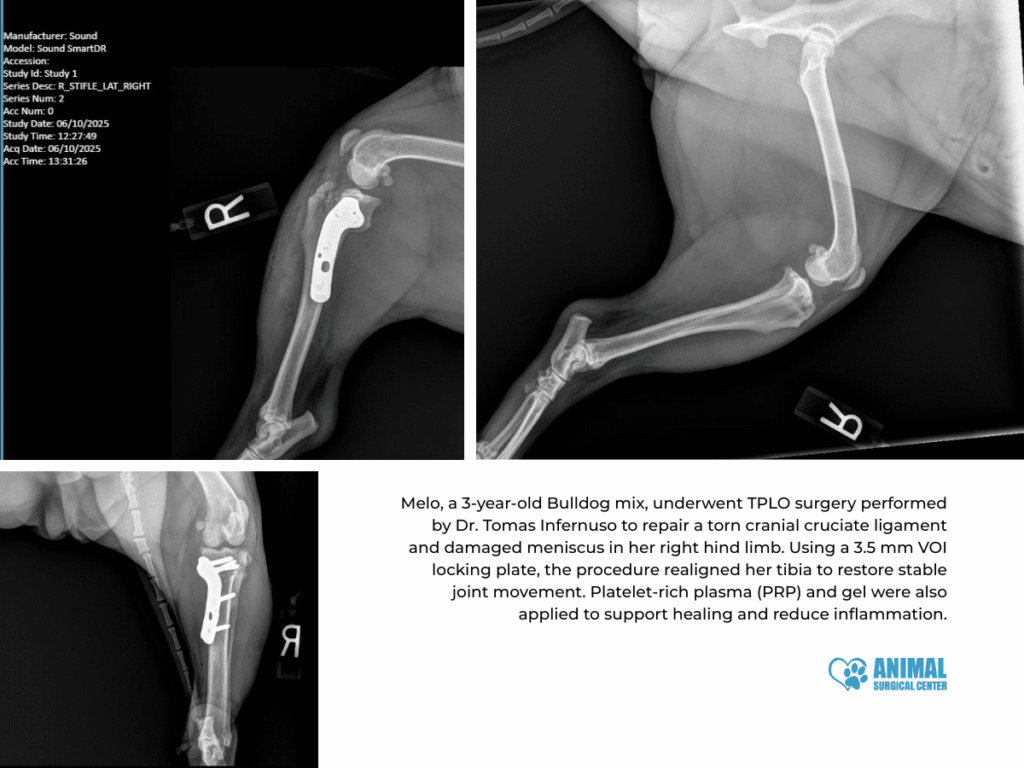

Case Study 1: Melo (TPLO Surgery)

- Patient: Melo, 3-year-old Bulldog Mix, 22.3 kg

- Presenting Concern: Limping on the right hind limb

- Exam Findings: Positive cranial drawer, joint effusion

- Surgery Date: June 10, 2025

Procedure: A routine TPLO was performed, along with a partial medial meniscectomy. A 3.5 mm locking plate was used for stability, and PRP + gel therapy supported her post-op healing.

Recovery: Melo is doing well and scheduled for her 2-week recheck. Her prognosis is excellent.